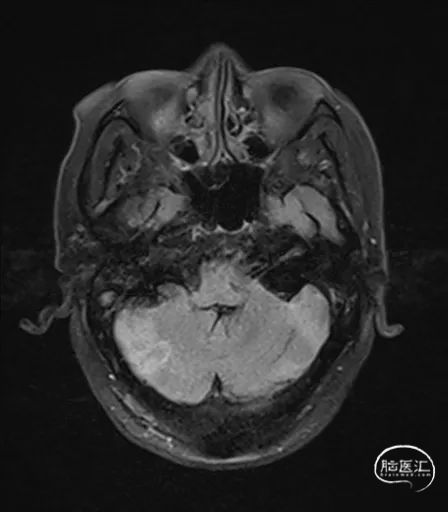

MRI提示小脑缺血性改变。

术后9天MRI: